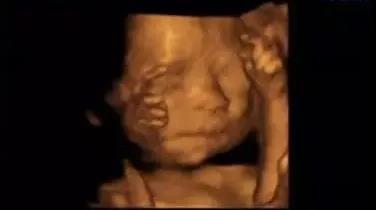

為了提前探尋這一“真相”

我們可以通過一個(gè)特別的儀式

在影像中讓寶寶與爸爸媽媽提前相遇

感受寶寶與父母奇妙的連接

這一切,只需要選擇四維彩超就可以啦

福利二:四維/5D彩超曬照集贊有禮

曬照需配上文字“雅安恒博醫(yī)院四維/5D彩超+自己想說的話”,集贊滿88個(gè),即可獲得:

雅安恒博醫(yī)院送出的兒童音樂搖搖木馬一個(gè)+雅安奶滋坊提供的30元無門檻代金券一張。

1、四維彩超最佳時(shí)間是孕24—26周。